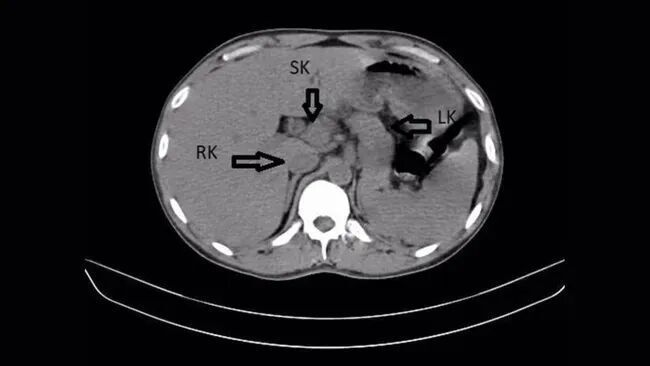

这张 CT 扫描图透露了患者右肾(RK)、“突出肾”(SK)以及左肾(LK)的位置。开始:Nimkar et al. Cureus (2022) doi: 10.7759/cureus.31436

在腹部超声和 CT 扫描下,大夫发现患者体内竟存在第三个肾脏,即所谓“突出肾”(supernumerary kidney)。该突出肾位于右侧,并与原有右肾承接,举座呈现出类似马蹄形的结构。